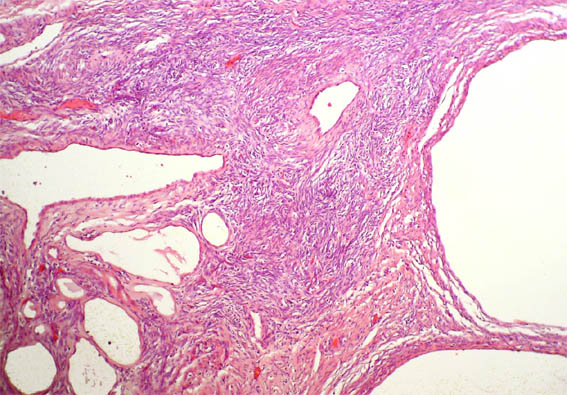

A 36-year-old woman presented with left flank pain for 2 months. She denied fever, gross hematuria, or body weight loss. Ultrasonography revealed a multicystic mass with multiple septa in the left kidney. Nephrectomy was done.

Figure 4. H&E, X200.